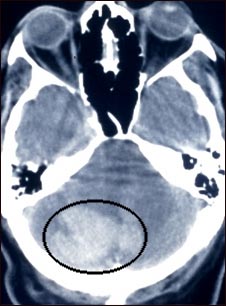

Tomografía computarizada de hemorragia intercerebral

Esta tomografía craneal muestra una hemorragia intracerebelar.